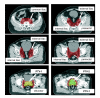

Methods: For ten patients with localized prostate cancer, IMRT plans with a simultaneous integrated boost (SIB) were generated for treatment of the prostate only (plan-PO) and for additional treatment of the pelvic lymph nodes (plan-WP). In plan-PO, doses of 60 Gy and 74 Gy (33 fractions) were prescribed to the seminal vesicles and to the prostate, respectively. Three plans-WP were generated with prescription doses of 46 Gy, 50.4 Gy and 54 Gy to the pelvic target volume; doses to the prostate and seminal vesicles were identical to plan-PO. The risk of rectal, bladder and small bowel toxicity was estimated based on NTCP calculations.

Results: Doses to the prostate were not significantly different between plan-PO and plan-WP and doses to the pelvic lymph nodes were as planned. Plan-WP resulted in increased doses to the rectum in the low-dose region </= 30 Gy, only, no difference was observed in the mid and high-dose region. Normal tissue complication probability (NTCP) for late rectal toxicity ranged between 5% and 8% with no significant difference between plan-PO and plan-WP. NTCP for late bladder toxicity was less than 1% for both plan-PO and plan-WP. The risk of small bowel toxicity was moderately increased for plan-WP.